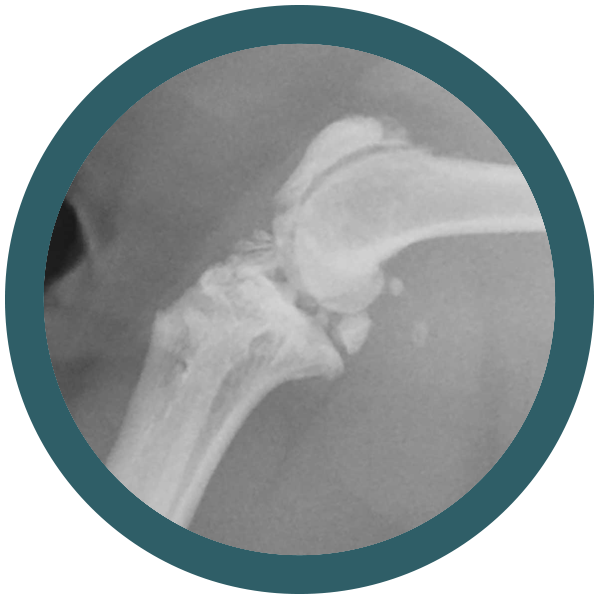

Il tuo gatto è un compagno fedele e amorevole che ti dà gioia ogni giorno. Ma anche i gatti possono soffrire di problemi ortopedici.

La buona notizia è che ci sono molti modi per prevenire i problemi ortopedici nei gatti. Una dieta sana e nutriente, esercizio fisico quotidiano e controlli regolari dal veterinario possono aiutare a mantenere il tuo gatto in forma e sano. Ma cosa succede se il tuo gatto ha un problema ortopedico? In questo caso interveniamo noi di Ortovet.

Siamo una rete di specialisti ortopedici veterinari e offriamo un servizio di elevata qualità, con l’utilizzo delle tecniche chirurgiche più avanzate. I nostri medici veterinari sono esperti nel trattamento di una vasta gamma di problemi ortopedici nei gatti

Come riconoscere una displasia dell’anca nel gatto

Osteocondrodisplasia Scottish Fold: quando la dolcezza delle orecchie nasconde un problema serio